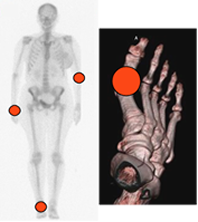

La articulación metatarsofalángica del 1º dedo es la más comúnmente afectada, seguida de las interfalángicas de los pies y las manos. (3). (Fig 31).

Fig 31. Distribución de la artropatía por gota.

Compromiso asimétrico con predominio en manos y pies.